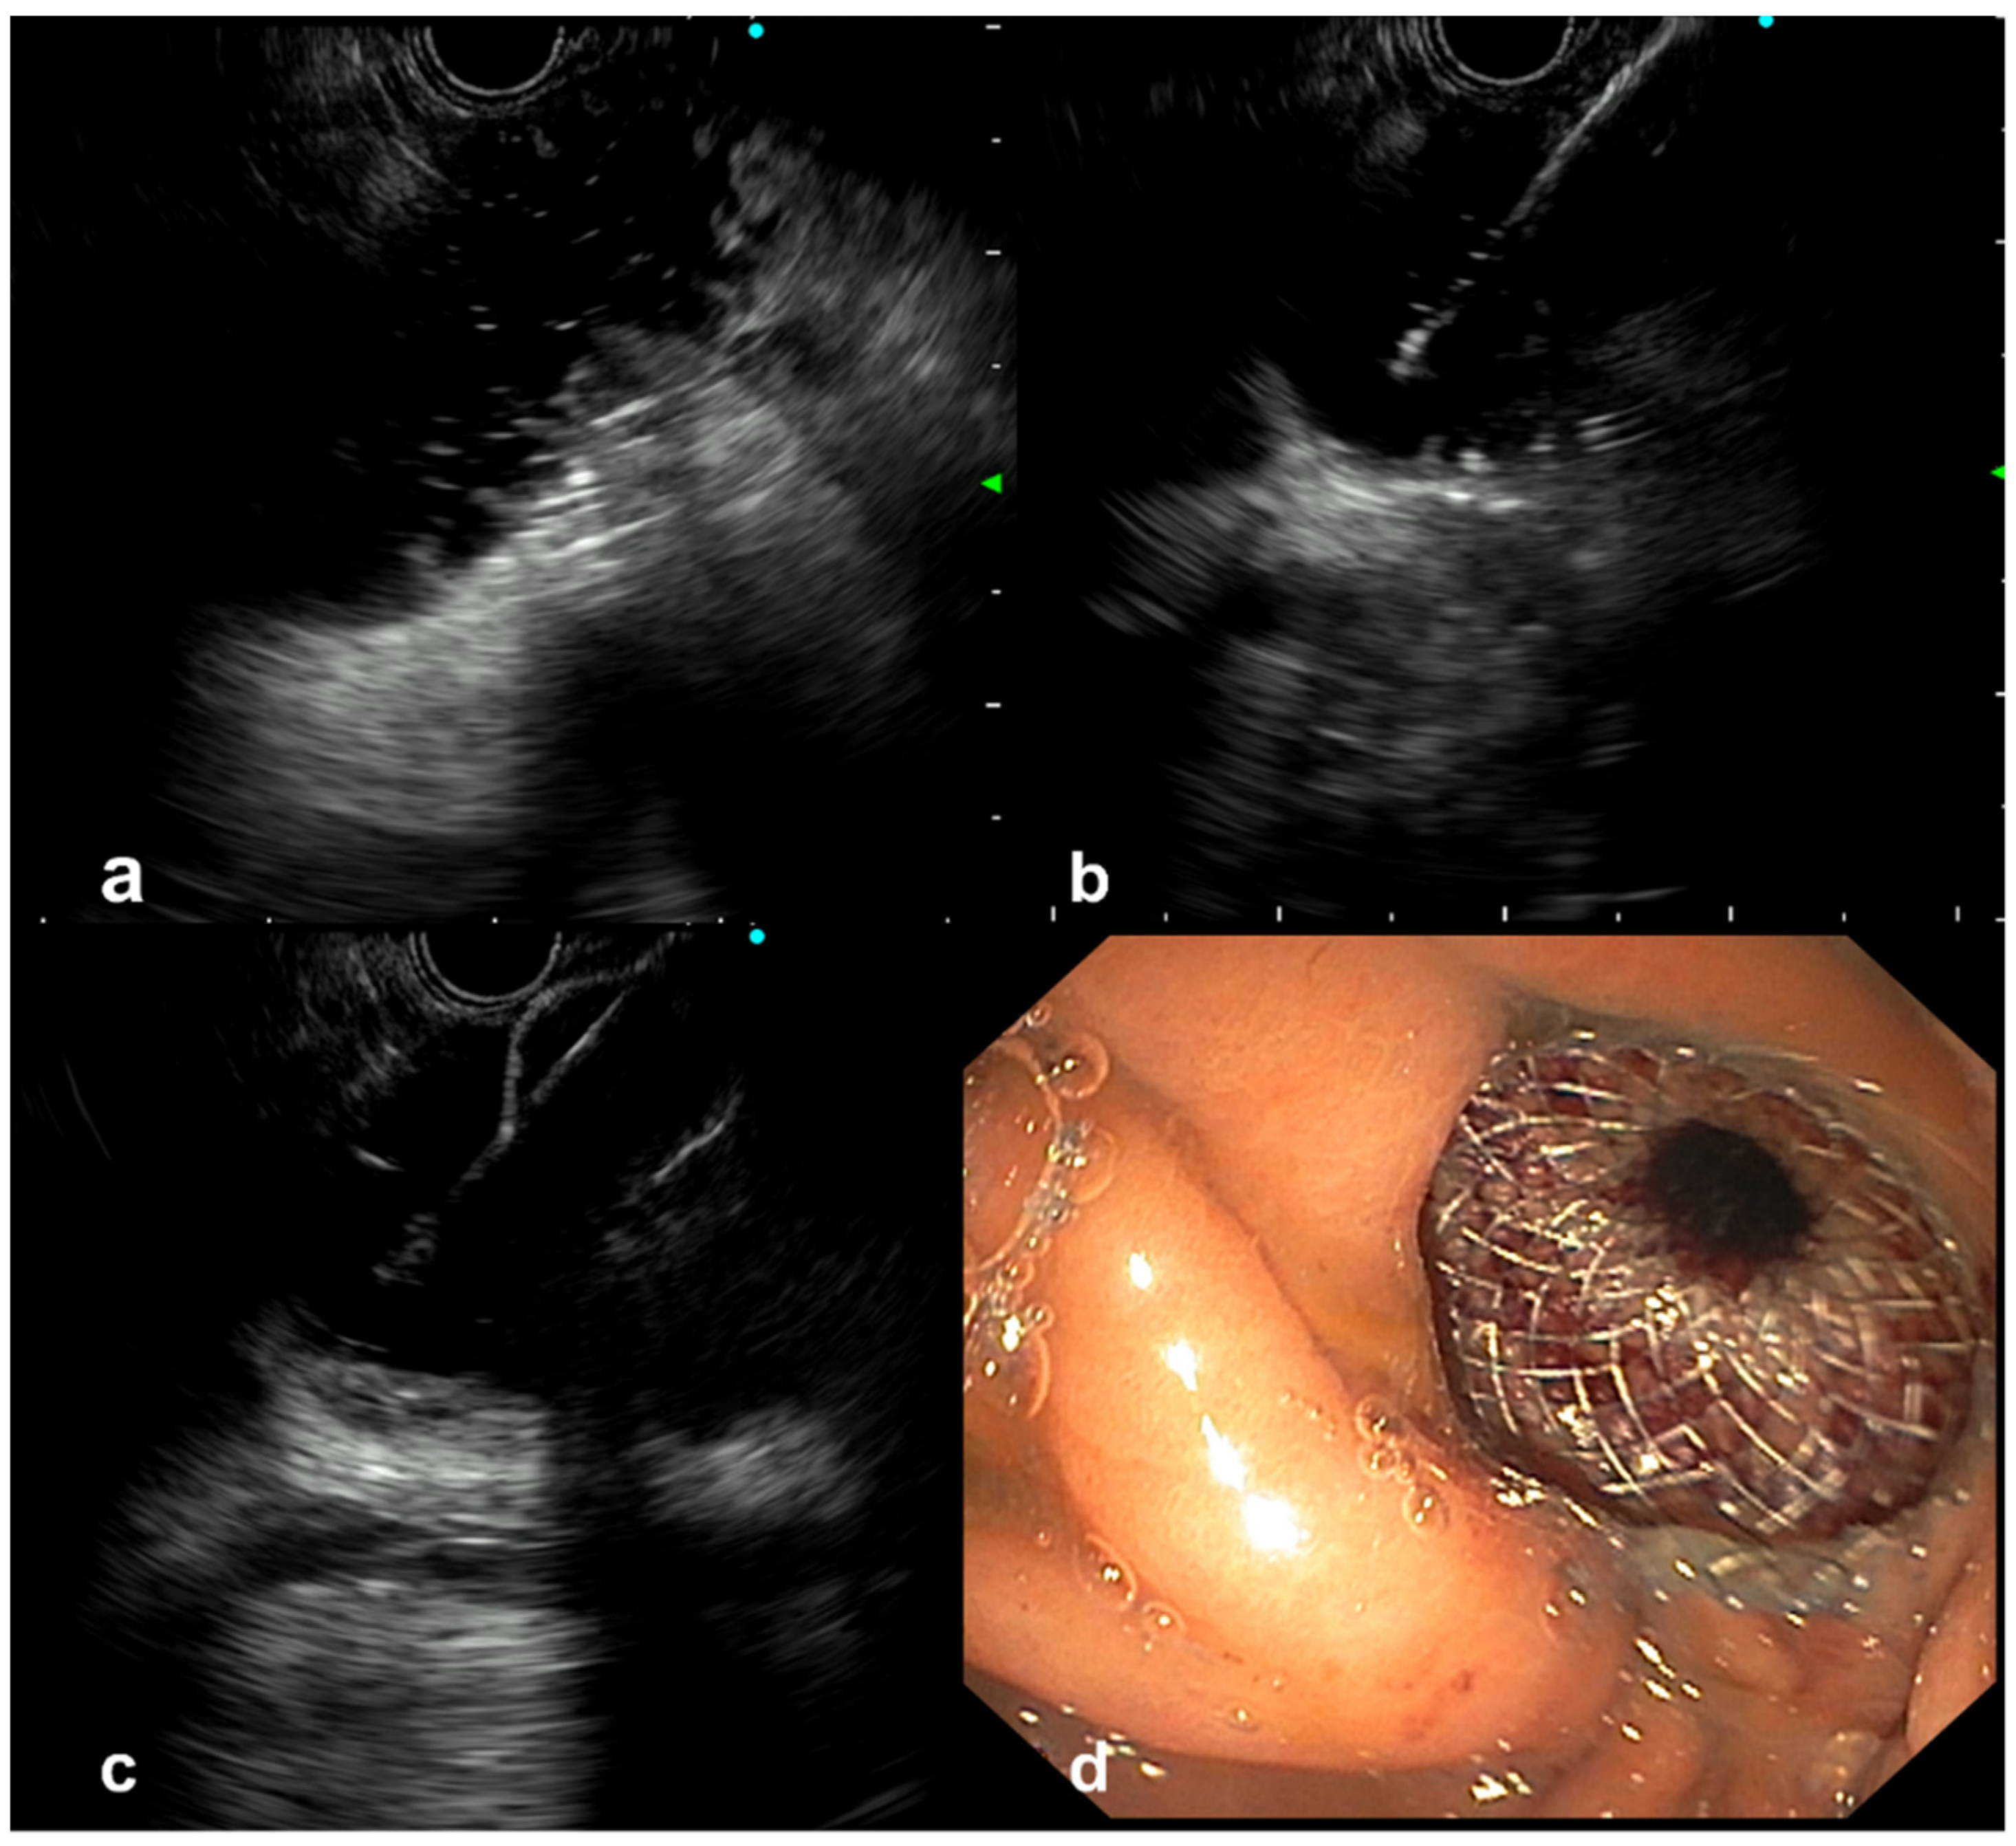

2.2. The EUS-GE Procedure